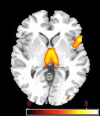

Effect of RGS4 genotype on functional connectivity, right VLPFC seed. Image depicts positive correlation between the number of A alleles and working memory-related network connectivity with right VLPFC reference region. Unthresholded image; color bar represents t score values.

Figure 3.

Effect of RGS4 genotype on functional connectivity, left VLPFC seed. Image depicts positive correlation between the number of A alleles and working memory-related network connectivity with left VLPFC reference region. Unthresholded image; color bar represents t score values.